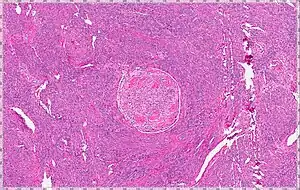

Intravenous leiomyomatosis is a rare condition seen exclusively in women in which leiomyomata, benign smooth muscle tumors, are found in veins. The masses are benign-appearing but can spread throughout the venous system leaving the uterus and even cause death when growing into the heart from the IVC.[1] While the possibility that these arose de novo from the smooth muscle in the blood vessel wall was considered, chromosomal analysis suggests a uterine origin.[2] Intravenous leiomyomata are usually but not always associated with uterine fibroids, and tend to recur.